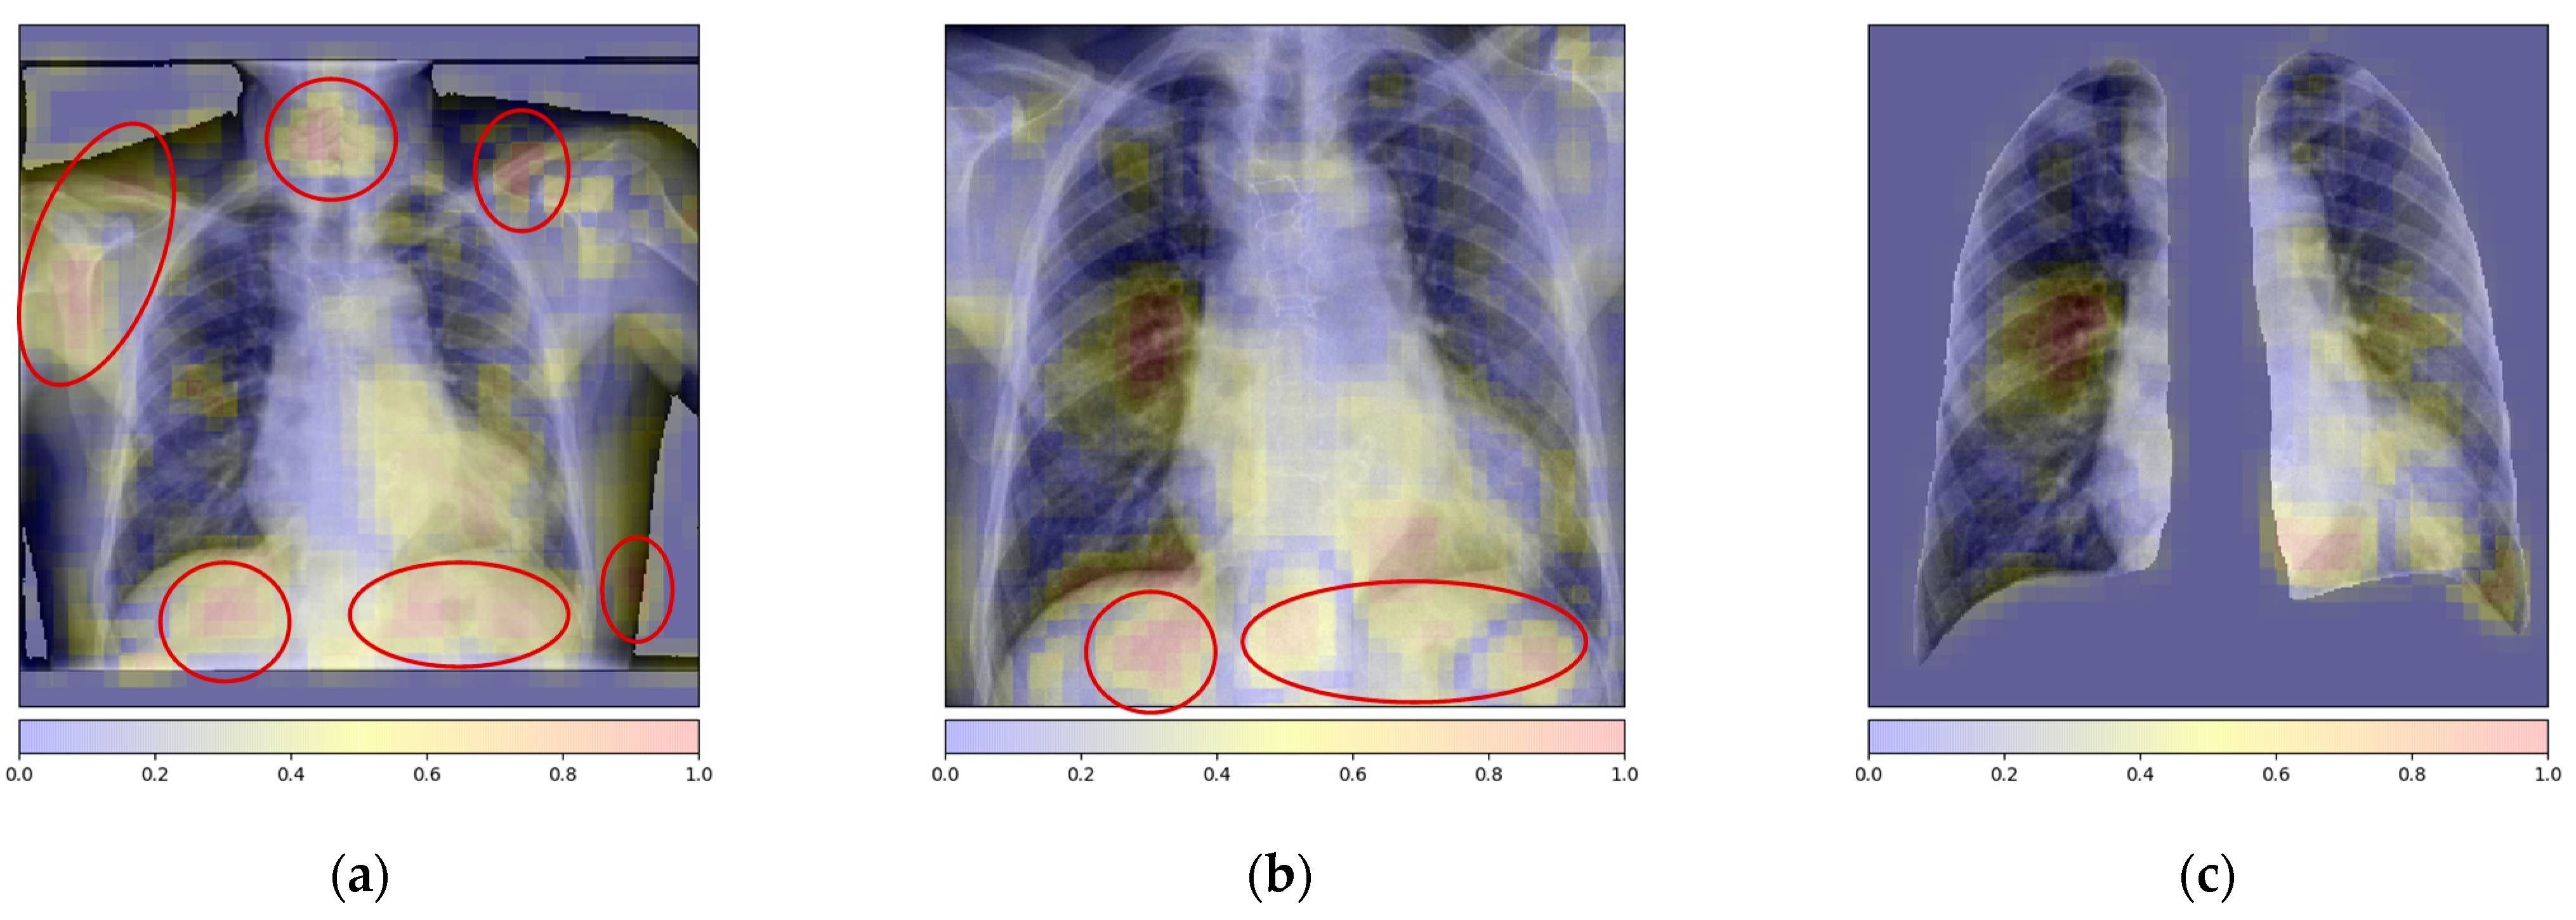

3.2.1. Lung Localization

Attention-Based Local Feature Extraction